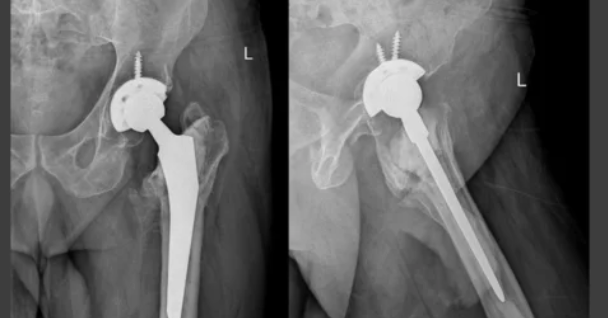

② 고관절 반치환술

대퇴골 쪽만 인공관절로 교체하는 방식입니다.

주로 고령자의 고관절 골절에서 시행됩니다.

- 건강보험 적용 시

→ 본인부담금 약 250만~500만 원 전후

전체 치환술보다

수술 범위가 작아

비용도 상대적으로 낮은 편입니다.